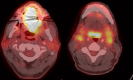

Case presentation: A 51-year-old male patient with human immunodeficiency virus and on highly active antiretroviral therapy (HAART) presented with a cT4aN2c SCCa of the tongue. He received a preoperative single course of Quad-Shot radiation therapy to 14 Gy in 4 fractions followed by surgical resection. Patient had no residual carcinoma on surgical pathology and no evidence of disease on subsequent clinical and radiological exams.